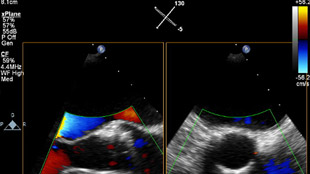

清晰的图像有助于您识别出那些符合经导管主动脉瓣修复手术条件的患者。

QLAB 可靠的量化数据。